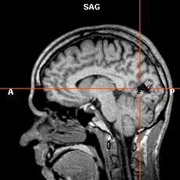

Исследователи из Рейкъявика выявили ген, изменения в котором приводят к развитию наиболее распространенных форм инсульта, сообщает The New York Times. Исследователи из Рейкъявика выявили ген, изменения в котором приводят к развитию наиболее распространенных форм инсульта, сообщает The New York Times. Как заявляют сотрудники компании Decode Genetics, изменения в новом гене являются не менее значительным фактором риска, чем артериальная гипертензия, повышенный уровень холестерина или курение. Найденный ген ранее никогда не связывался исследователями с инсультом, и его открытие может привести к новым методам профилактики и лечения этого заболевания. Однако, как отмечают специалисты, говорить о новых подходах в терапии инсульта пока рано: открытие исландских ученых должно быть подверждено в других научных работах. Кроме того, в исследовании принимали участие жители Исландии, что не гарантирует наличия идентичных генетических изменений в других популяциях. Кроме инсульта, группа исследователей из Рейкъявика под руководством Сольвейг Гретарсдоттир (Solveig Gretarsdottir) работала с другими распространенными заболеваниями, которые принято считать мультифакторными, и обнаружила 12 генов и 20 хромосомных участков, изменения в которых играют большую роль в возникновении этих патологий. Mednovosti.ru Другие Новости в этой рубрике • Как побороть авитаминоз• Обжорство полезно • Чем нам грозит всего одна чашечка кофе в день? • Аспирин: кратчайший путь к стоматологу • Факты об антибиотиках • По мнению европейцев, американская еда провоцирует рак • 80 миллионов женщин и детей могут умереть от бедности до 2015 года • 93-летняя женщина выпрыгнула из окна из-за ошибки ''скорой помощи'' • Еврокомиссия намерена заставить европейцев отказаться от курения • Гормон, регулирующий аппетит, поможет похудеть • Журнал Science опроверг статью о вреде экстази • Ученые намерены исследовать людей, переживших клиническую смерть • Канадцы назвали ''государственную'' марихуану отвратительной • SARS снова покинул человеческую популяцию • Возбудитель тяжелой пневмонии обитает в водопроводе • Британцы думают, что рак заразен и провоцируется разводом • Прививка от оспы спасает от СПИДа • Мобильники приводят к преждевременному старению мозга • Вакцину от малярии испытают на африканцах • Таинственная болезнь американцев в Ираке вызвана сигаретами |